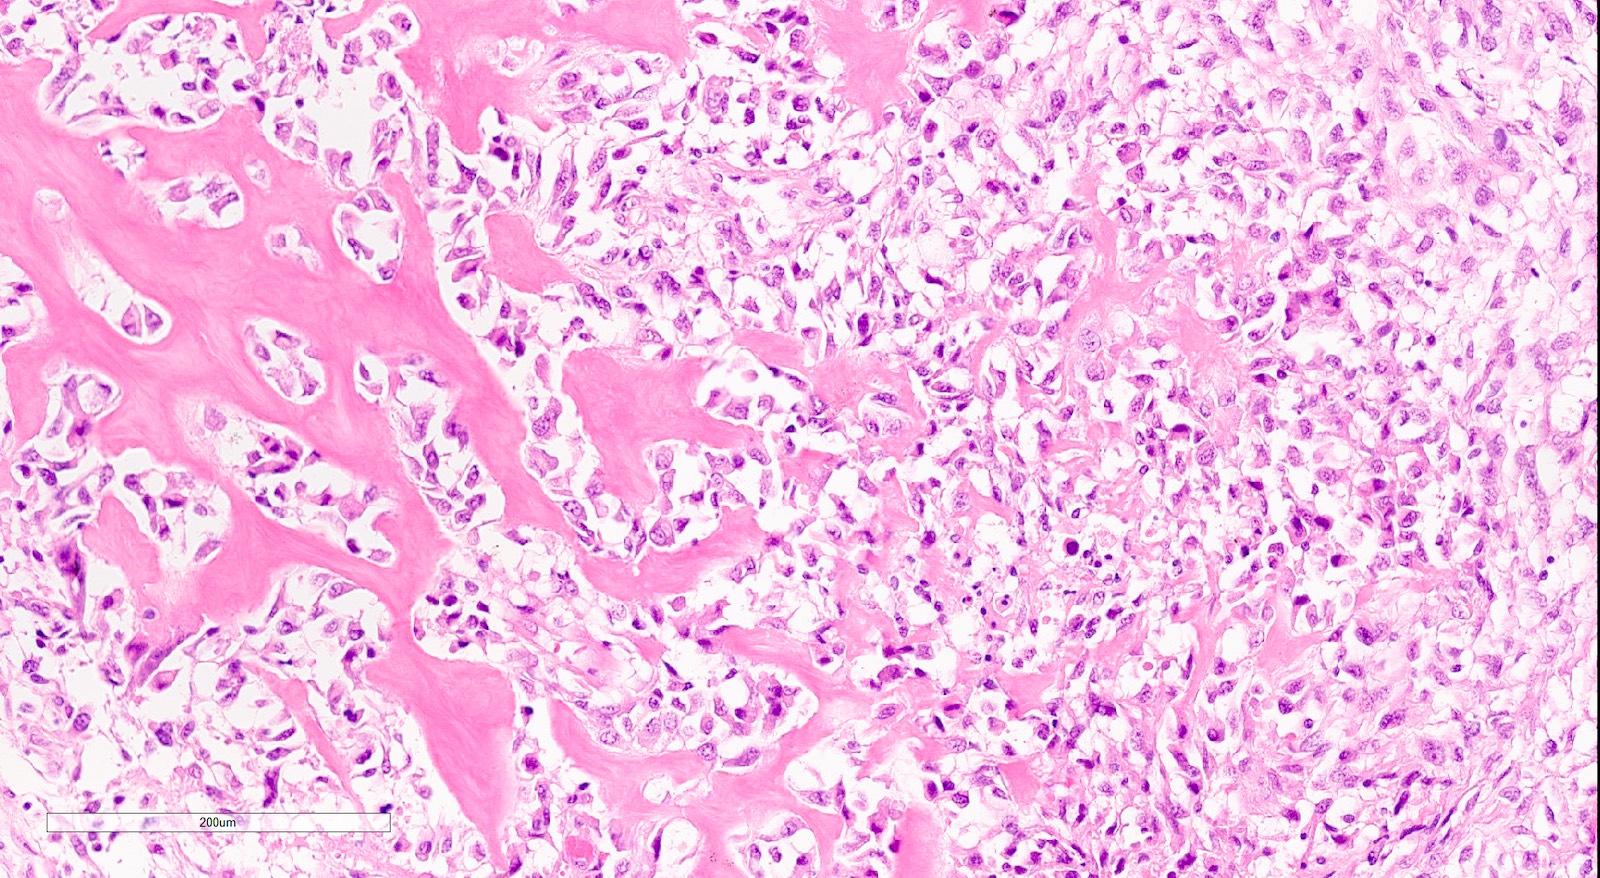

Microscopic (histologic) description

- Biphasic tumor with carcinomatous and sarcomatous elements, both high grade (Int J Gynecol Pathol 1990;9:1)

- Carcinomatous and sarcomatous components are juxtaposed

- Carcinomatous elements:

- Often high grade endometrioid or serous carcinoma, frequently admixed

- More uncommonly clear cell carcinoma

- 50 - 75% of cases have serous or mixed serous and high grade endometrioid carcinoma (Am J Surg Pathol 2007;31:1653)

- Hybrid morphology between endometrioid and serous carcinoma is frequent, as is undifferentiated carcinoma (Mod Pathol 2010;23:781)

- Other components that can be rarely found are squamous, mucinous and neuroendocrine

- Sarcomatous elements:

- Often spindle and pleomorphic

- 50% contain heterologous elements (most commonly rhabdomyosarcoma and chondrosarcoma) (Am J Surg Pathol 2007;31:1653)

- Osteosarcomatous, liposarcomatous and angiosarcomatous differentiation are less common (Semin Diagn Pathol 1988;5:199, Arch Pathol Lab Med 1991;115:583, Int J Gynecol Pathol 2017;36:140)

- Carcinomatous elements:

- Angiolymphatic invasion common, more commonly of the carcinomatous component

Microscopic (histologic) images